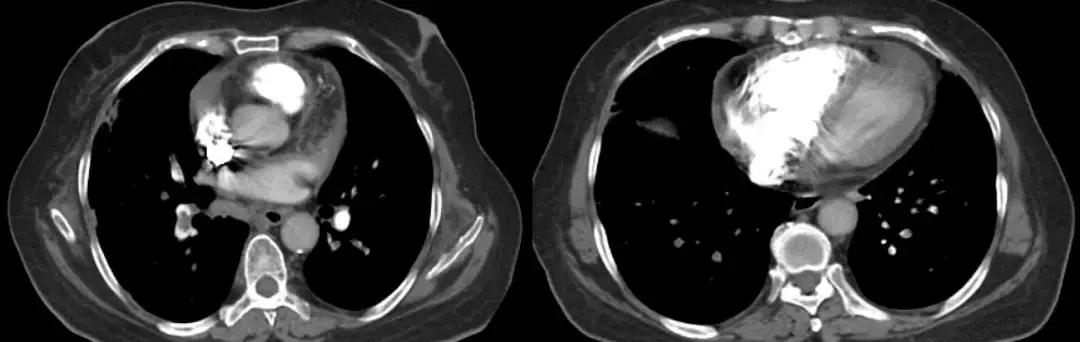

男,67岁,急性病程;发病前有旅游病史;主诉:发热、干咳伴呼吸困难2天,加重1天;查体:体温38.3℃,心率96次/分, 呼吸35次/分,血压98/63mmHg,SpO2 88%(FiO20.37),急性病容,呼吸急促,左肺呼吸音粗,右下肺呼吸音减弱,双下肺可闻及湿啰音;肺部CT示双下肺渗出、实变影,动脉血气分析提示I型呼吸衰竭。

2017-9-26

2017-9-29

双侧气管黏膜充血,可见大量脓黄痰,左下肺基底段灌注生理盐水50ml,回收20ml,送检细菌和真菌涂片、培养;7项呼吸道病原体;EB病毒核酸、巨细胞病毒核酸;抗酸杆菌涂片及染色、结核分枝杆菌鉴定及药敏。最终结果回报:H1N1和金黄色葡萄球菌(MSSA)。降级抗生素为阿莫西林克拉维酸钾联合奥司他韦抗病毒治疗,患者症状好转出院。

经验教训

甲型流感病毒感染后可能出现继发细菌(肺炎链球菌、金黄色葡萄球菌、流感嗜血杆菌等)和曲霉感染,一定注意病原检测,不要过度依赖于强大的抗细菌药物。